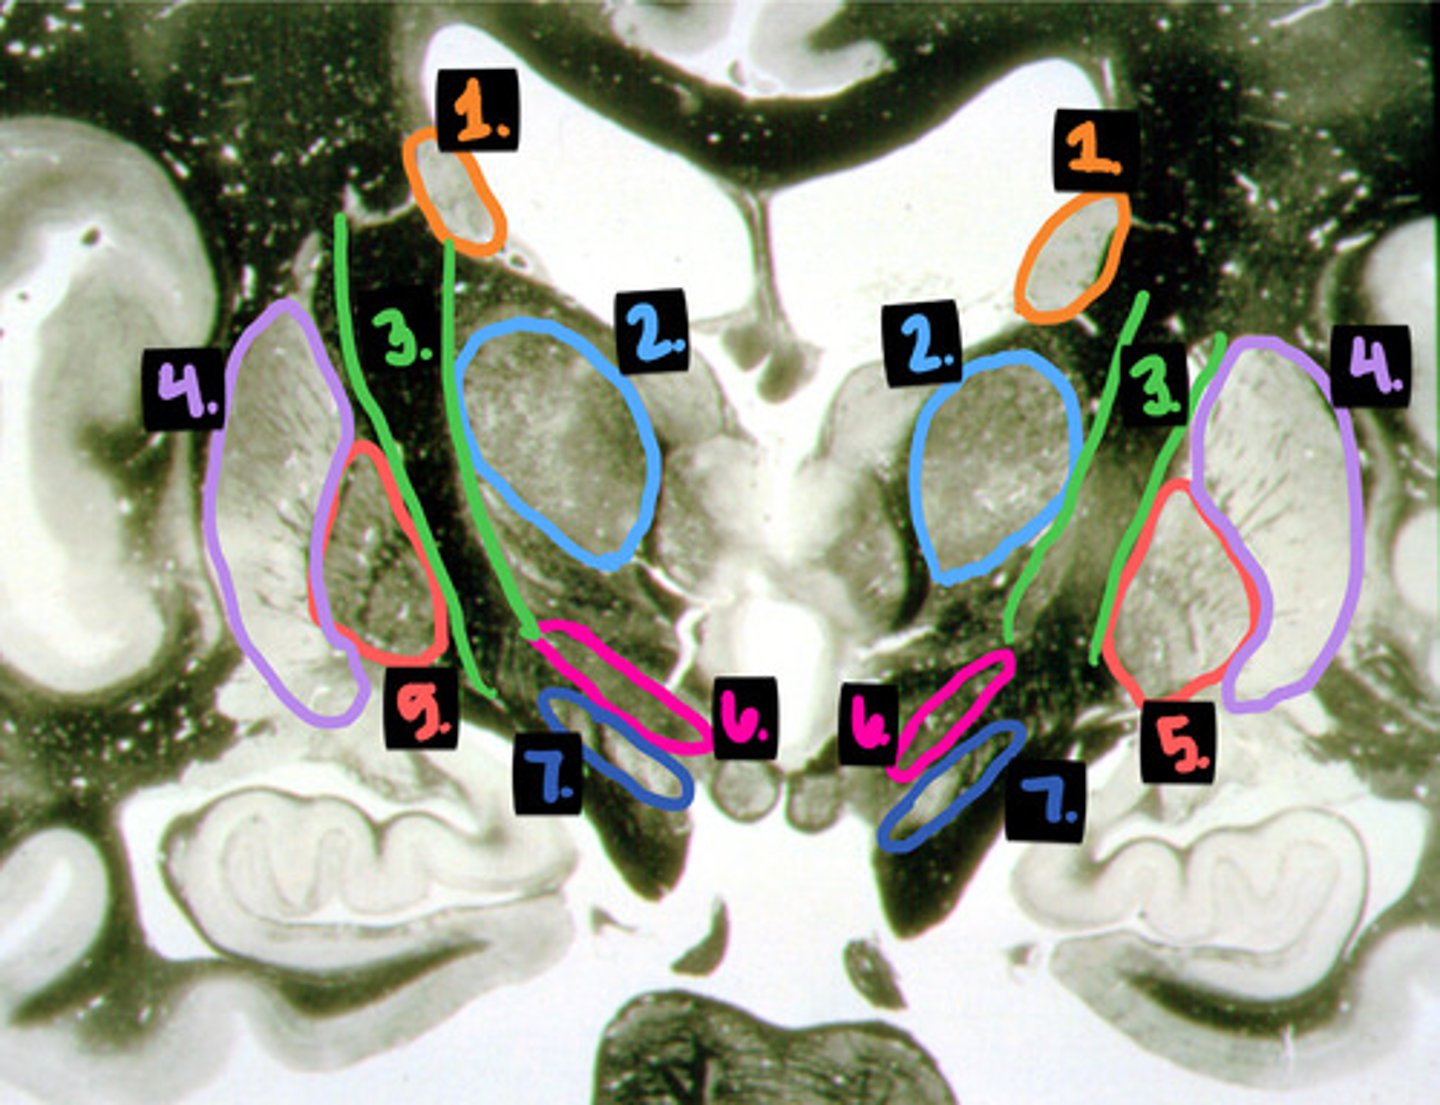

hearing (part of the auditory pathway)

what is the function of the medial geniculate nucleus?

vision (part of the visual pathway)

what is the function of the lateral geniculate nucleus?

contralateral somatosensation from the body

what is the function of the ventral posterolateral nucleus?

contralateral somatosensation from the face

what is the function of the ventral posteromedial nucleus?

motor control

what is the function of the ventral anterior/lateral nuclei?

limbic system

what is the function of the anterior and lateral dorsal nuclei?

interpreting and learning written symbols

what is the function of the pulvinar and lateral posterior nuclei?

emotions, moods, feelings, personality

what is the function of the dorsal nucleus?